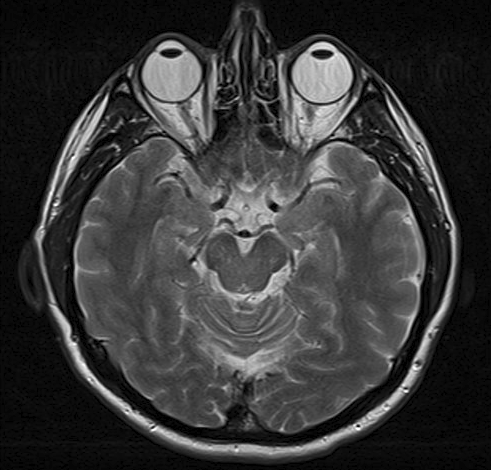

Dieses Bild ist ein MRT-Scan eines Gehirns. Die Augäpfel der Person sind oben im Bild zu sehen.

MRI-Scan

Von Ptrump (Eigenes Werk) via Wikimedia Commons